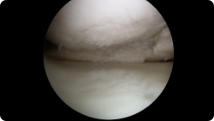

Arthroscopic image of a miniscus tear Arthroscopic image of a miniscus tear after knee arthroscopy

Miniscus Tear

After Knee Arthroscopy